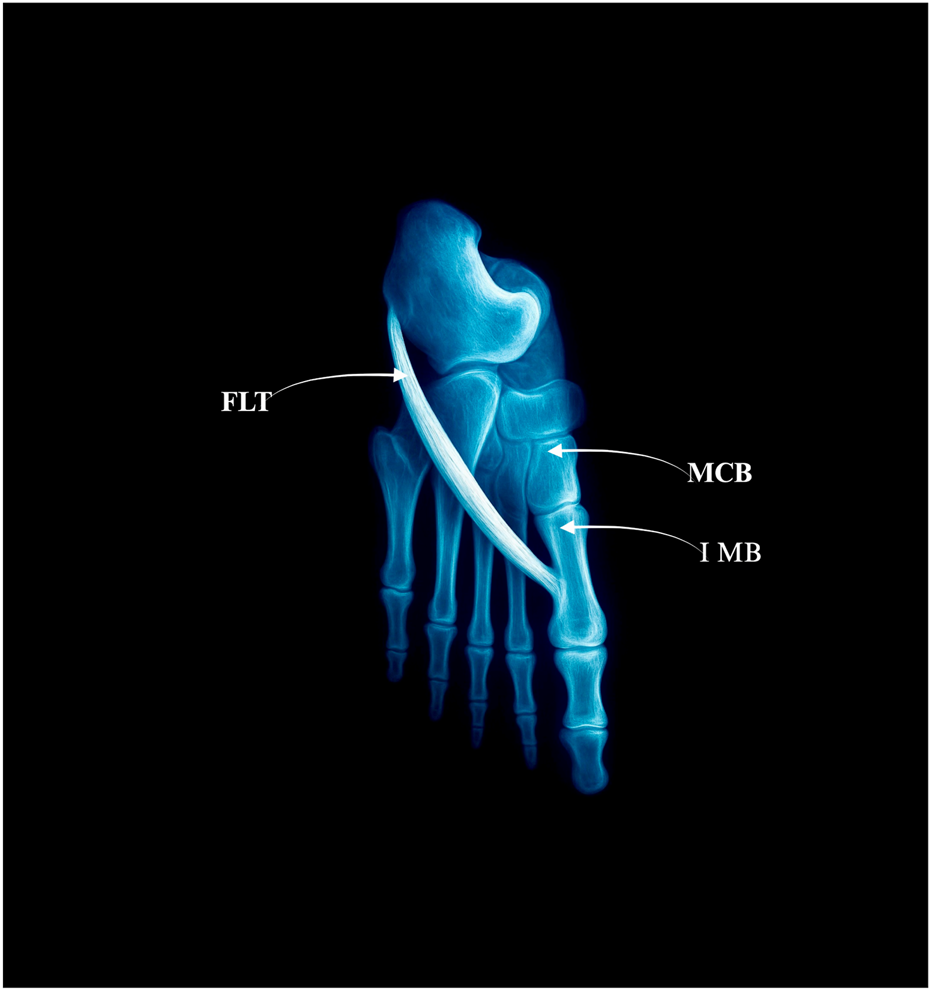

The FLT inserts solely into the lateral tubercle of the base of the first metatarsal bone–Figure 1.

Figure 1. Type I: single distal insertion to the lateral tubercle of the base of the first metatarsal. Abbreviations: FLT fibularis longus tendon; 1 MB the first metatarsal bone. MCB–medial cuneiforme bone.

3.4.2 Type II–Bifurcated distal attachment

The main tendon inserts into the same lateral tubercle, but additional accessory slips branch off.

• Prevalence: 40 limbs (40%)

• Subtypes:

○ IIa–Accessory slip to the medial cuneiform (28 cases) – Figure 2a.

○ IIb–Strong accessory slip to both the base of the first metatarsal and the medial cuneiform, involving also the first metatarsal-cuneiform joint (9 cases) = Figure 2b.

○ IIc–Accessory slip to the first dorsal interosseous muscle (3 cases) – Figure 2c.

Figure 2. Type II of fibularis longus tendon. (a) Type IIa of the fibularis longus tendon. (b) Type IIb od the fibularis longus tendon. (c) Type IIc od the fibularis longus tendon. FLT–fibularis longus tendon. MCB–medial cuneiforme bone. IMB–first metatarsal bone. I IDM–first dorsal interosseous muscle.